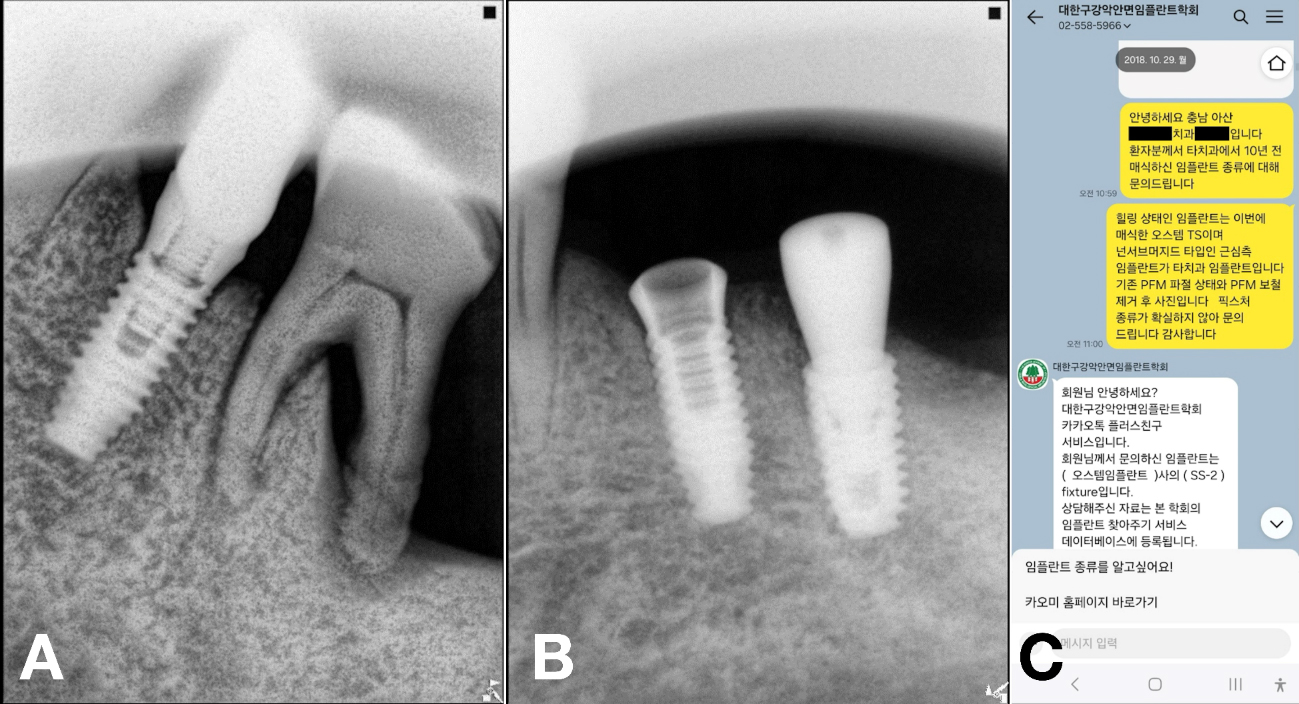

In South Korea, the Korean Academy of Oral and Maxillofacial Implantology (KAOMI) provides an “Implant Finder” service, allowing clinicians to submit radiographic images of unknown implants via designated social media platforms (e.g., KakaoTalk). Submitted images are cross-referenced with a comprehensive implant database, and identification results are returned through the same channel. Although the service demonstrates reliable and efficient identification, to the best of our knowledge, no reports have yet demonstrated its clinical application or successful outcomes.

A 69-year-old male presented with discomfort in the left mandibular molar region. Tooth #36 was deemed hopeless and subsequently extracted, whereas the adjacent #35 implant exhibited a fractured crown on an existing undocumented fixture.6, 7 Two months after a GBR with a FDBA at site #36, a new implant (TSIII, 4.5 mm diameter and 8.5 mm length; Osstem Implant) was placed with an initial torque of 35 Ncm. A healing abutment (5 mm diameter, and 7 mm height) was simultaneously placed. As the implant at site #35 remained undocumented, the KAOMI team again was consulted. The fixture was identified as SS-2 (SS-2; Osstem Implant) (Fig. 7).

An appropriate stock abutment for fixture (#35) was procured, enabling reuse of the existing implant for patient comfort and reduced surgical morbidity. The restoration was completed based on the information provided by the implant finder service (Fig. 8A and 8B).